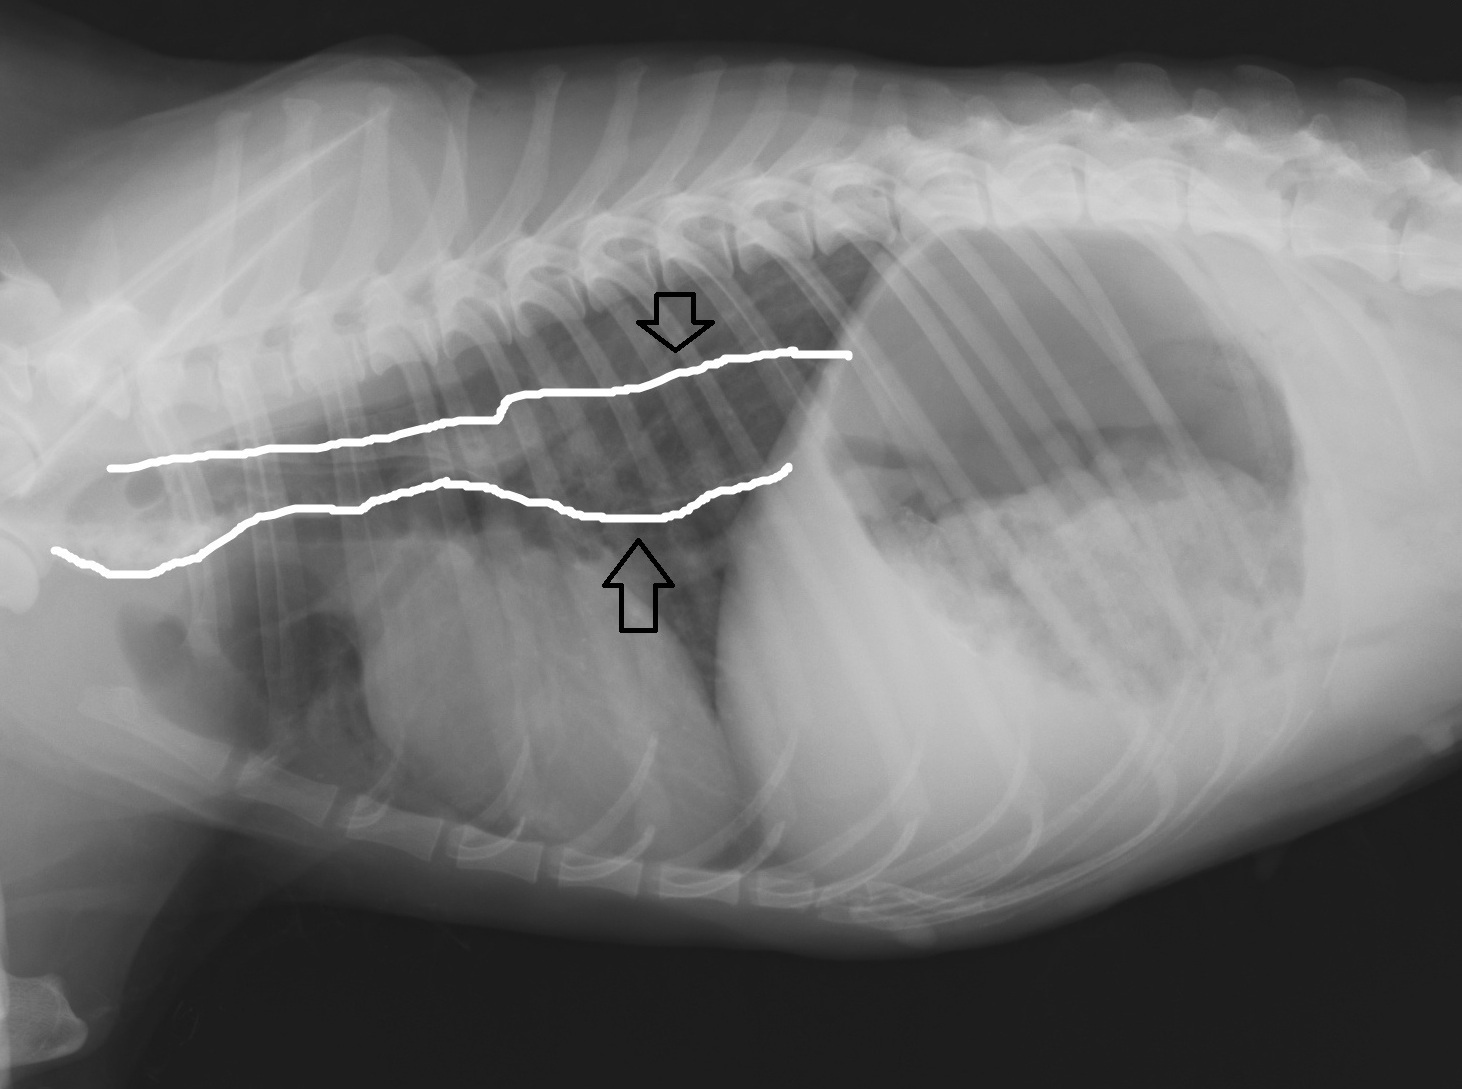

犬の巨大食道症、誤嚥性肺炎どうぶつ病院京都 四条堀川京都市。

食道拡張 巨大食道症 ♢消化器疾患♢院長ブログ。

巨大食道症尼崎の動物病院アニマルプラス。

巨大食道症診療コラム南が丘動物通信南が丘動物病院 兵庫県三田市の動物病院。

犬の巨大食道症草村動物病院 「動物の診察室から」。

巨大食道症宇賀ペットクリニック。